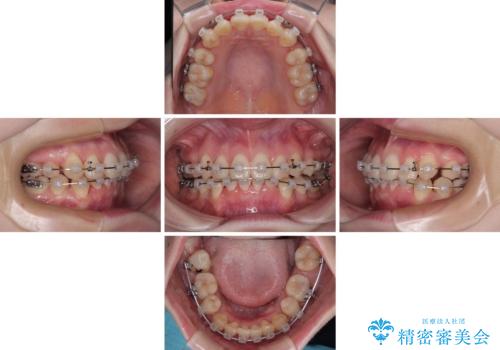

上下の八重歯とクロスバイト ワイヤー装置での抜歯矯正

- クリアブラケット

- 1年4ヶ月

- 八重歯とクロスバイトを気にして来院された患者様です。

上下ともに八重歯が顕著であり、前歯のクロスバイトがあったため、上下左右の第一小臼歯4本を抜歯し、ワイヤー装置での抜歯矯正を行うこととしました。

20歳ということもあり、歯の移動速度が非常に速く、1年強という短期間であっという間に治療を終えることができました。